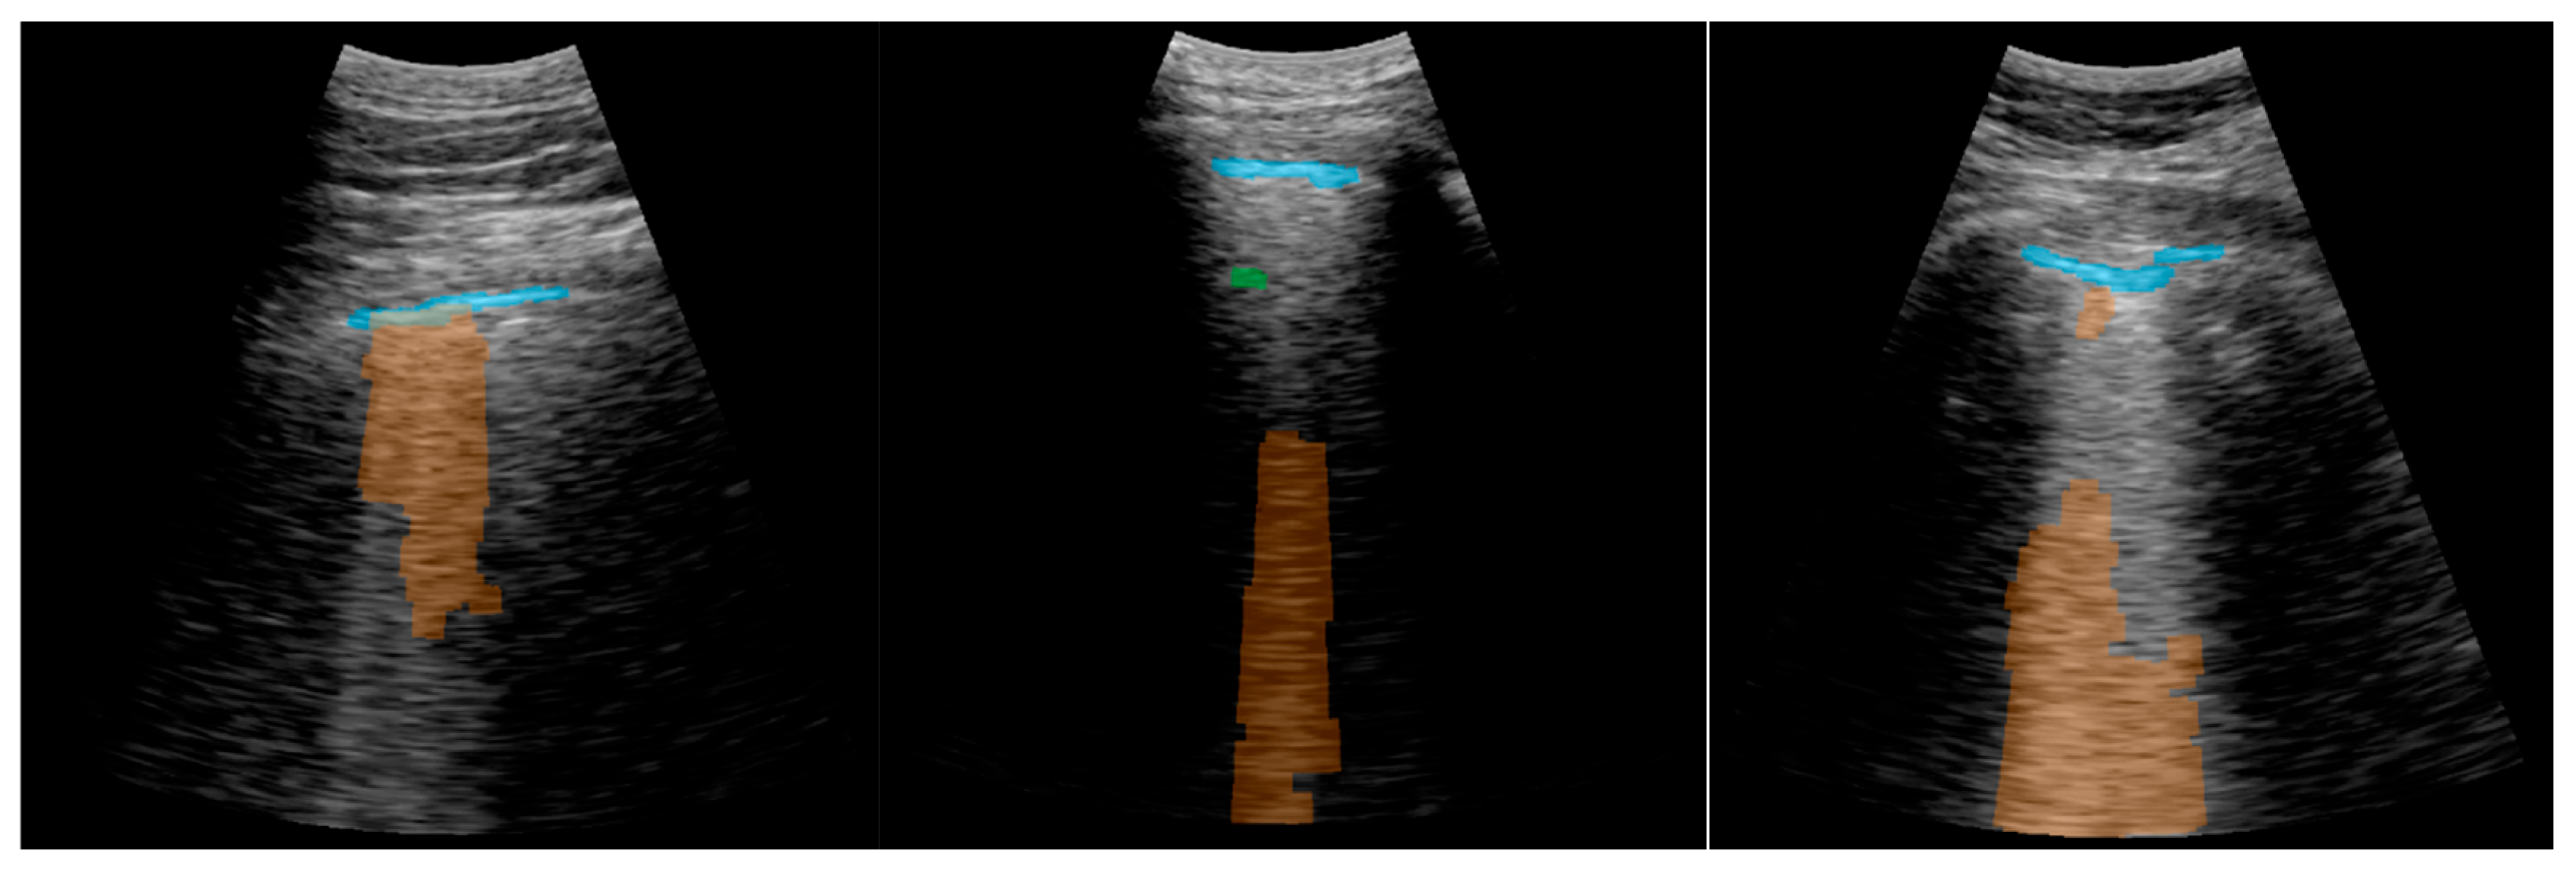

Figure 16 shows several examples of the screen of the implemented software in operation explained in Section 2.5.4.

Figure 16.

Application visualization sample: (a) B-lines (orange) and consolidation (red) detection; (b) normal lung with A-lines (green); (c) probe movement detected; (d) B line (orange) and A-line (green) deteccion on a Lung phantom. On the right of each image the C-scan image is shown.